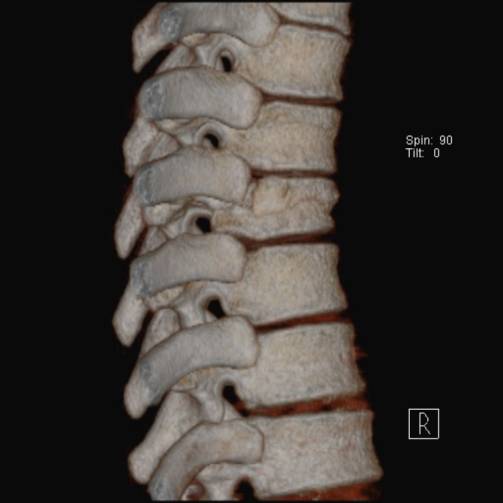

Chance 骨折

胸腰段椎体的分离性骨折,伴随脊髓、神经根、椎体的水平方向的崩裂骨折。